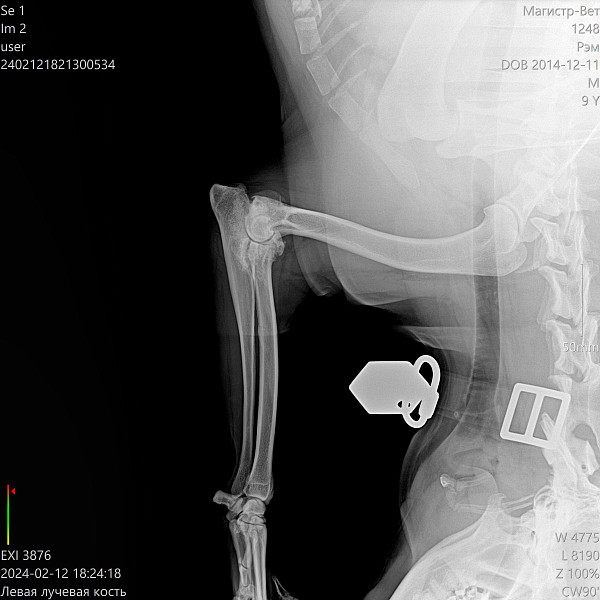

Здравствуйте! Проконсультируйте, пожалуйста. Лабрадор-ретривер, кобель, 9 лет, не кастрирован, вес 38 кг., питание сухой корм ТМ "SIRIUS", хромает на левую переднюю лапу. Рентген прилагаю. В ветклинике предлагают операцию по удалению медиального венечного отростка, при этом говорят хромота останется. Есть ли смысл в такой операции, или существуют другие способы и методы лечения? Как избавить собаку от боли? Сейчас нам назначили мелоксикам 7,5 мг: 1 день 1/2 табл. 1 р. в день, со 2 дня 1/4 табл. 1 р. в день. всего 6 дней. А дальше что делать? Это ведь не панацея.

Пес очень активный, любит гулять, как можно помочь ему с таким суставом? Какие вообще прогнозы при таком рентгене?

Добрый день. У вашей собаки к сожалению существенные дегенеративные изменения локтевого сустава. Оперативное вмешательство с целью удаления венечного отростка может не дать положительного эффекта, но может слегка облегчить состояние. Сустав не восстановить! Можно под контролем узи ввести в полость сустава противовоспалительные препараты и гиалуроновую кислоту, но для начала проконсультируйтесь с ортопедом. Худеть! Ограничение физических нагрузок.